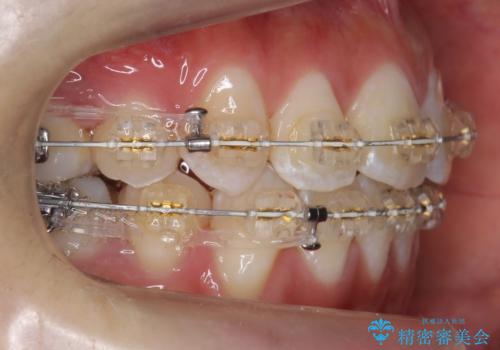

八重歯の治療 仕上がり重視で

- 八重歯を主訴に来院。

仕上がり重視とのことで、小臼歯を抜歯し、スタンダードな治療方法で仕上げています。

上下の小臼歯を抜歯しています。

矯正用インプラントアンカーを使用してしっかり前歯を下げたため、口元が大きく改善しています。